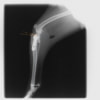

本症例は、走った後に左後肢を挙上していることを主訴に来院されました。触診時に左膝関節のクリック音を聴取、レントゲン検査にて左脛骨の前方変位が認められました。術中に、前十字靱帯の断裂及び内側半月板の損傷、内側の軟部組織の顕著な腫脹を確認。半月板切除、TPLOを実施しました。周囲組織への炎症の波及もあったため回復に時間を要しておりますが、徐々に跛行頻度は減少傾向にあり、現在も経過観察中です。術前に約29°あったTPAは術後に約10°まで矯正されました。

術後写真

手術前後のTPA(脛骨高平部の角度)を測定しています。

約29°から約10°へ矯正されています。